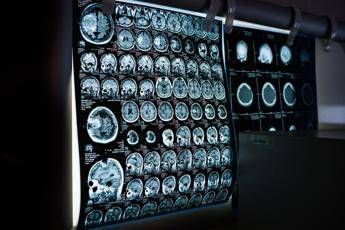

(Adnkronos) – In occasione della Giornata mondiale delle malattie rare 2026, che si celebra il 28 febbraio, la Società italiana di neurologia (Sin) rinnova il proprio impegno nel promuovere attenzione, consapevolezza e azioni concrete per i pazienti affetti da malattie neurologiche rare, un ambito che rappresenta una delle aree più complesse e in continua evoluzione. Queste patologie – informa la società scientifica in una nota – comprendono centinaia di condizioni differenti, spesso di origine genetica, che possono manifestarsi in età pediatrica o adulta e che sono frequentemente caratterizzate da un decorso progressivo e da un importante impatto funzionale. Nel loro insieme, queste patologie interessano un numero rilevante di persone e pongono sfide significative non solo sul piano clinico ma anche organizzativo, sociale ed economico, coinvolgendo l’intero sistema sanitario. Nonostante i progressi della ricerca scientifica e delle tecnologie diagnostiche, persistono ancora significativi ritardi nella diagnosi, percorsi assistenziali frammentati e disuguaglianze territoriali nell’accesso ai centri di riferimento e alle cure, con rilevanti ripercussioni sulla qualità della vita delle persone e delle loro famiglie. "La Giornata mondiale delle malattie rare è un momento cruciale per riaffermare che queste patologie non devono rimanere ai margini dell’attenzione sanitaria e istituzionale – afferma Mario Zappia presidente Sin – Le malattie neurologiche rare interrogano profondamente la neurologia contemporanea, chiamandoci a ripensare i modelli di diagnosi, presa in carico e continuità assistenziale. Come Sin, siamo impegnati a promuovere una neurologia capace di riconoscere precocemente queste condizioni, accompagnare i pazienti lungo tutto il percorso di malattia e sostenere la ricerca clinica e traslazionale come strumento concreto di cambiamento". Un elemento centrale per migliorare la gestione delle malattie neurologiche rare – secondo gli esperti – è rappresentato dalla standardizzazione dei percorsi diagnostico-terapeutici, attraverso raccomandazioni condivise, algoritmi clinici e strumenti operativi che possano supportare il neurologo nella pratica quotidiana, anche al di fuori dei centri altamente specialistici. "Le malattie neurologiche rare, in particolare quelle di origine genetica, richiedono competenze specialistiche ma anche un approccio strutturato e condiviso”– sottolinea Massimiliano Filosto, coordinatore del Gruppo di studio Sin di Neurogenetica clinica e malattie rare – Il lavoro del Gruppo di studio è orientato alla definizione di best practices, allo sviluppo di algoritmi diagnostici e gestionali e alla formazione dei neurologi. Ridurre il ritardo diagnostico significa oggi offrire ai pazienti un accesso più tempestivo alle cure". Negli ultimi anni, il panorama delle malattie neurologiche rare è stato profondamente trasformato dalla disponibilità di terapie innovative che stanno cambiando in modo concreto la storia naturale di alcune patologie. Tra queste rientrano, a titolo di esempio, le terapie enzimatiche sostitutive, le terapie di riduzione del substrato, gli oligonucleotidi antisenso, le terapie geniche e altre strategie avanzate attualmente in sviluppo clinico. Questi approcci terapeutici, già disponibili o in fase avanzata di sperimentazione per diverse condizioni neurologiche rare – illustrano i neurologi – rendono ancora più urgente una diagnosi tempestiva e una corretta stratificazione clinica dei pazienti. In molti casi, infatti, l’efficacia delle terapie è strettamente legata alla precocità dell’intervento e alla preservazione delle funzioni neurologiche residue. "L’innovazione terapeutica sta aprendo scenari impensabili fino a pochi anni fa per molte malattie neurologiche rare – evidenzia Filosto – Perché queste opportunità possano tradursi in benefici reali, è fondamentale che i pazienti vengano intercettati precocemente e indirizzati in percorsi strutturati e competenti". In questo contesto, la collaborazione con le associazioni di pazienti assume un valore certamente centrale. "Le terapie innovative rappresentano una grande speranza, ma anche una sfida per la sostenibilità del sistema sanitario – osserva Annalisa Scopinaro, presidente di Uniamo, Federazione italiana malattie rare – È essenziale garantire equità di accesso, informazione corretta e continuità di cura. Il dialogo con la Sin e con la comunità scientifica è fondamentale per assicurare che i progressi della ricerca si traducano in diritti concreti e in una migliore qualità della vita per tutte le persone con malattia rara". A tale proposito la Sin ribadisce il proprio impegno per: promuovere formazione e aggiornamento continuo sulle malattie neurologiche rare; sostenere progetti di consensus, linee di indirizzo clinico e algoritmi condivisi; favorire il lavoro in rete tra centri specialistici, territorio e istituzioni e rafforzare la collaborazione con le associazioni dei pazienti. Un impegno che nasce dalla convinzione che occuparsi di malattie neurologiche rare significhi investire in una neurologia più moderna, equa e orientata al futuro, capace di coniugare innovazione scientifica, appropriatezza clinica e centralità della persona.